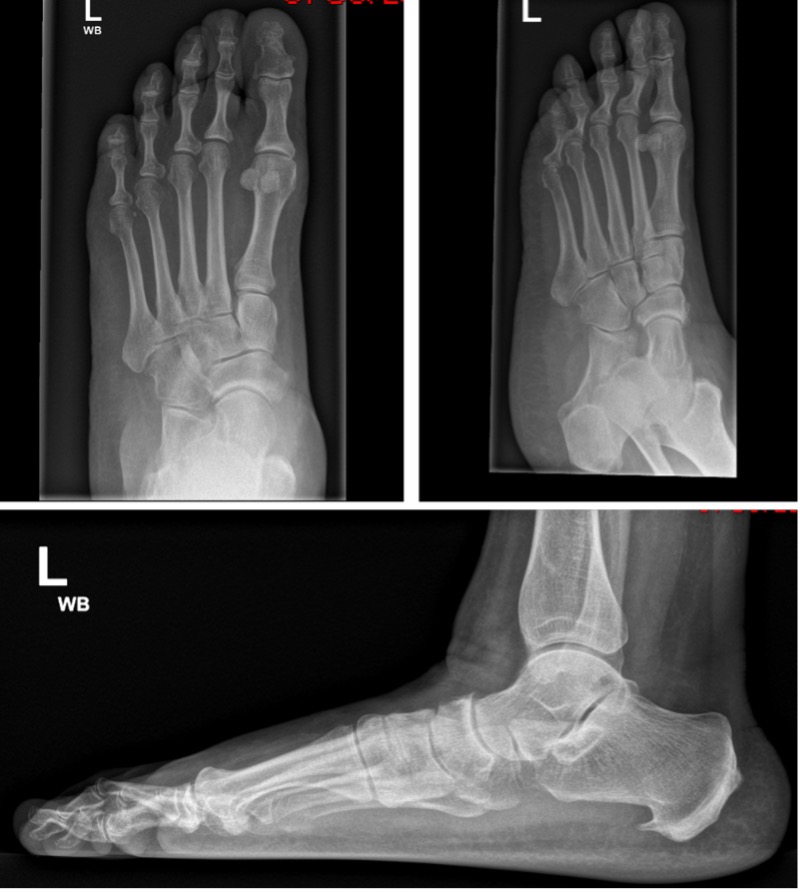

- Weightbearing AP and lateral, oblique foot radiographs (Fig 7); assess for:

- Talo-first-metatarsal alignment on AP and lateral (Meary’s angle)

- Apex of deformity

- Talonavicular coverage angle

- Calcaneal pitch angle

- Arthritic changes

- Other deformities (hallux valgus)

Figure 7: Standing AP, oblique and lateral showing talar head uncovering and loss of Meary’s angle (J&S Stage IIA disease)

Figure 8: Standing AP and lateral showing bilateral talar head uncovering and loss of Meary’s angle (J&S Stage IIB disease)